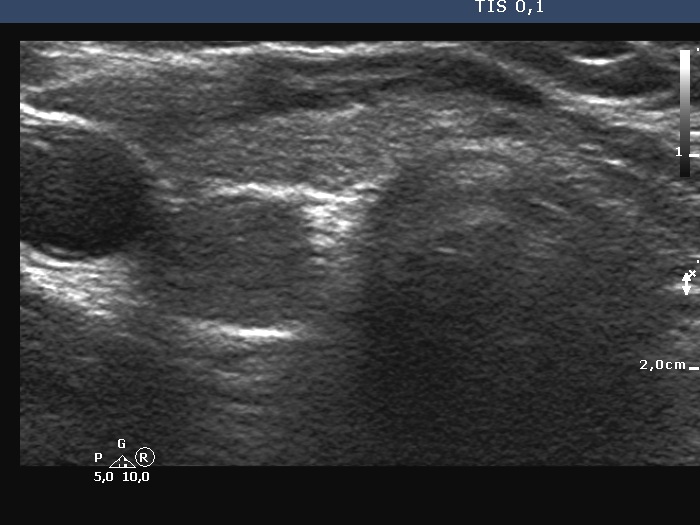

Ultrasonography. The thyroid was echonormal and had some minimally hypoechoic areas. A thick connective tissue band crossed the right lobe. Dorsal to this fragment the thyroid was very hypoechoic. On transverse scan, this area seemed to be a nodule. However, analysis of multiple sections revealed that this area was not a true nodule.

The echogenicity of a specific tissue is deeply influenced by ventral structures. The well-known examples are the cystic fluid and the macrocalcification. The first can cause acoustic amplification, i.e. the dorsal structures become lighter, more echoic, while the macrocalcification has the opposite effect, the so-called acoustic shadowing makes the dorsal tissue very hypoechoic.

In this boy, the thick connective tissue hindered the penetration of the ultrasound wave, therefore the dorsal structure became darker, hypoechoic. -